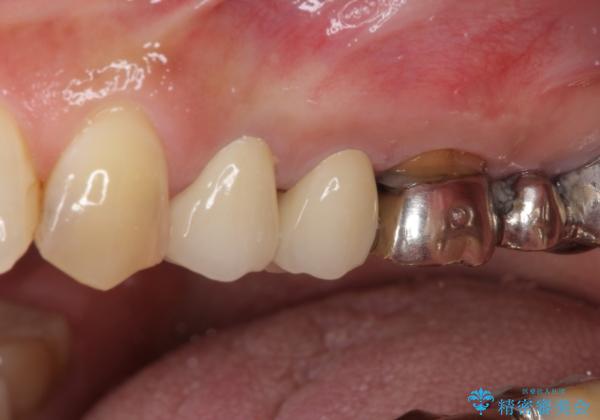

- 歯肉が退縮したためにクラウンの縁や歯根が見えてしまっていることを気にして来院された患者様です。

強い咬合力や磨きすぎなどにより、歯根が見えてしまったり、金属の縁が見えてしまったりし、審美障害を引き起こすことがあります。

歯根が変色してしまうと、歯肉越しに歯根の黒い色が透けてしまうことがあり、この点についてはどうにも施しようがないため、患者様には事前のご理解いただきました。